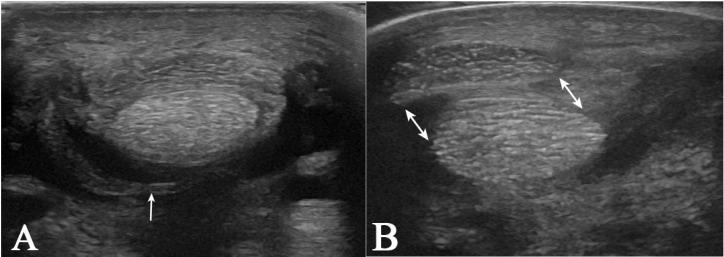

Diagnosing digital flexor tendon sheath (DFTS) pathologies, particularly manica flexoria (MF) tears, can be challenging with standard imaging modalities. Standing low-field MRI tenography (MRIt) may improve the detection rate of MF tears. This study aimed to compare ultrasonography, contrast radiography, pre-contrast MRI, and MRIt to detect naturally occurring MF lesions in horses undergoing tenoscopy. Ten horses with a positive DFTS block, which underwent contrast radiography, ultrasonography, MRI, MRIt, and tenoscopy were included. Two radiologists evaluated the images and recorded whether an MF lesion was present and determined the lesion side. Sensitivity and specificity were calculated for each modality using tenoscopy as a reference. MRIt and contrast radiography detected MF lesions with the same frequency, both showing 71% sensitivity and 100% specificity. Pre-contrast MRI and ultrasonography detected MF lesions with a lower sensitivity (57%); however, the MRI (100%) demonstrated a higher specificity than ultrasonography (33%). Adding contrast in MRI changed the sensitivity from (4/7 lesions) 57% to (5/7 lesions) 71%, with a constant high specificity (100%). MRIt diagnoses MF tears with a similar sensitivity to contrast radiography, with the same specificity, but with the added benefit of lesion laterality detection. The combined advantages of the anatomical detail of the T1 sequence and the post-contrast hyperintense appearance of the fluid may help diagnose MF tears and identify intact MFs. However, this needs to be substantiated in a larger number of cases.

摘要

诊断指屈肌腱鞘(DFTS)病变,尤其是屈肌总腱鞘(MF)撕裂,采用标准成像方式具有挑战性。站立位低场MRI肌腱造影(MRIt)可能提高MF撕裂的检出率。本研究旨在比较超声检查、造影X线摄影、造影前MRI和MRIt,以检测接受关节镜检查的马匹中自然发生的MF病变。纳入10匹DFTS阻滞阳性且接受了造影X线摄影、超声检查、MRI、MRIt和关节镜检查的马匹。两名放射科医生评估图像,记录是否存在MF病变并确定病变侧。以关节镜检查为参考,计算每种检查方式的敏感性和特异性。MRIt和造影X线摄影检测到MF病变的频率相同,敏感性均为71%,特异性均为100%。造影前MRI和超声检查检测MF病变的敏感性较低(57%);然而,MRI(100%)的特异性高于超声检查(33%)。MRI中添加造影剂后,敏感性从(4/7个病变)57%变为(5/7个病变)71%,特异性保持较高(100%)。MRIt诊断MF撕裂的敏感性与造影X线摄影相似,特异性相同,但还具有检测病变侧别的额外优势。T1序列的解剖细节和造影后液体的高信号表现相结合的优势,可能有助于诊断MF撕裂并识别完整的MF。然而,这需要在更多病例中得到证实。